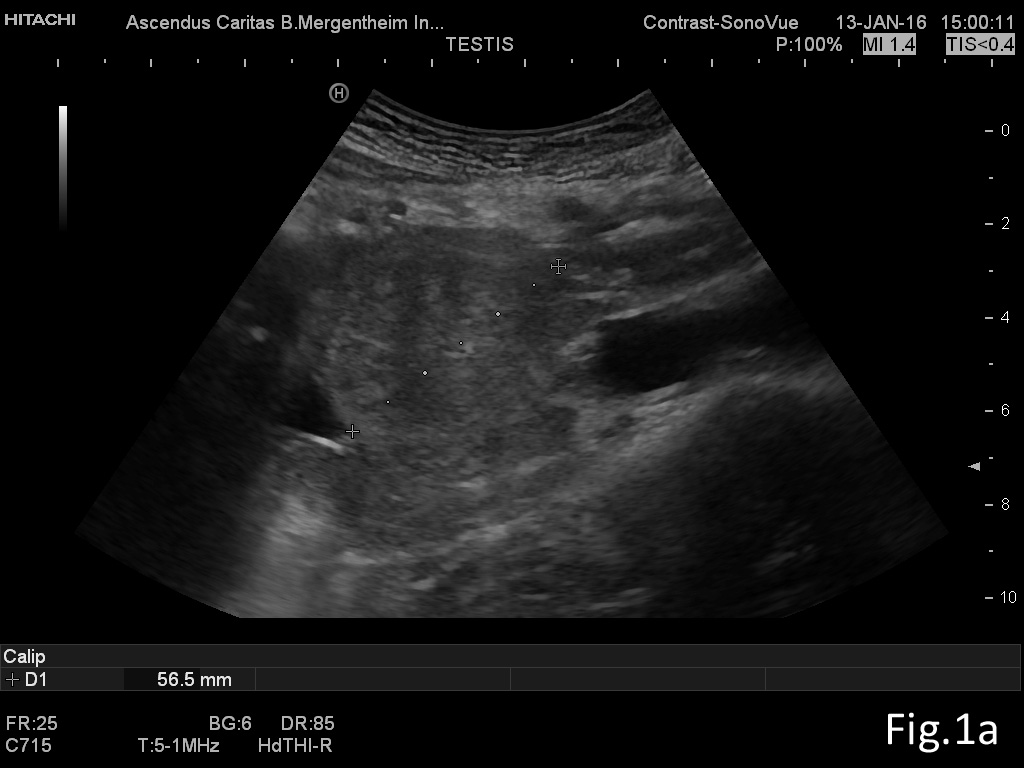

We report on a 28 year old male presenting with unspecific abdominal pain for two weeks. B-mode ultrasound revealed extended abdominal lymphadenopathy [Figure 1] and two small unspectacular hemangioma-like focal liver lesions [Figure 2]. The left testis revealed a palpable tumour by ultrasound also examined with elastography and contrast enhanced ultrasound [Figure 3 and 4]. Endoscopy of the upper gastrointestinal tract showed candida of the esophagus. The biopsy of the abdominal (retroperitoneal) lymph nodes revealed epithelial cells, typical for testicular embryonal cell carcinoma.

This case report illustrates the use of conventional and innovative ultrasound technologies for the differential diagnosis of (retroperitoneal) lymphadenopathy [(6-18)], focal liver lesions [(2;19-24)], and testicular masses [(25-32)] in daily routine [(33)]. The following text mainly refers to the published paper in Endoskopie Heute [(34)]. Testicular tumours account for <2 % of all malignancies in men and are thus considered rare. There is a marked age association with 20 - 40 year old patients (mean age 35) accounting for 20 - 30 % of all cases, and testicular tumours are the most common malignant tumour in this age group. The classic initial symptom in all testicular cancers is the painless, unilateral and slow increase in size of the testis but sometimes also unspecific symptoms elsewhere. Testicular tumours can be divided into germ cell and non-germ cell tumours. The most common histological type of germ cell tumour (and ultimately of all testicular tumours, 40%) is the seminoma. The seminoma appears sonographically as a hypoechoic, relatively sharply defined tumour without calcification or cystic structures. In our patient small calcifications could be seen. Non-seminomatous germ cell tumours include embryonal carcinomas (as in our case) teratocarcinomas, teratomas, choriocarcinoma, and yolk sac tumours. Mixed tumours are rare and show a variety of elastography appearances. Other tumours of the gonadal stroma, metastases and lymphomas have to be ruled out before surgery. Sonographic appearances of the Leydig cell tumour (2 % of all testicular tumours) cannot be differentiated from those of seminoma. The echo pattern is similar to seminomas, the Leydig cell tumour is usually smaller. Differential diagnosis has to take into account haematoma, and focal changes in granulomatous orchitis (anamnestic information). According to testicular imaging we also refer to the already mentioned published literature on imaging [(25-32)]. Other pathological entities include testicular cysts and (micro) calcifications. Microlithiasis is often observed in combination with a malignant testicular tumour in the surrounding parenchyma [(26)]. The value of elastography for early detection and avoidance of biopsy procedures has not been established so far but is promising [(34)]. Lymphatic drainage of the testis is ipsilateral, lateral to the para-aortic lymph nodes, located at the level of the renal vessels on the left, and slightly more caudally on the right. The case illustrates lymph node assessment criteria. For further reading we refer to the recently published literature [(7-9;14;35-37)]. Regarding CEUS of the liver [(24;38;39)], CEUS of non-liver organs [(39)], elastography [(40-44)], and ultrasound guided interventions [(45-53)] we refer to the EFSUMB guidelines [(54)].